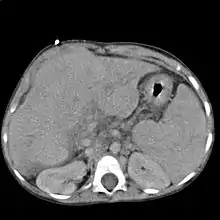

Imagerie

Elle est peu spécifique et sert essentiellement à détecter certaines causes rares ou des complications (cancer du foie).

L'échographie abdominale montre un parenchyme hépatique hétérogène et nodulaire, contours bosselés, avec une hypertrophie du segment I ou lobe caudé, des signes d'hypertension portale avec augmentation de la taille de la rate (splénomégalie)…

Le scanner et l'IRM sont meilleurs que l'échographie pour détecter un cancer du foie[2]. L'IRM est également fiable pour détecter certaines causes, notamment l'hémochromatose, par la mesure de la concentration en fer des tissus[15]. La fibroscopie œsogastrique peut retrouver des varices œsophagiennes, signe d'hypertension portale.